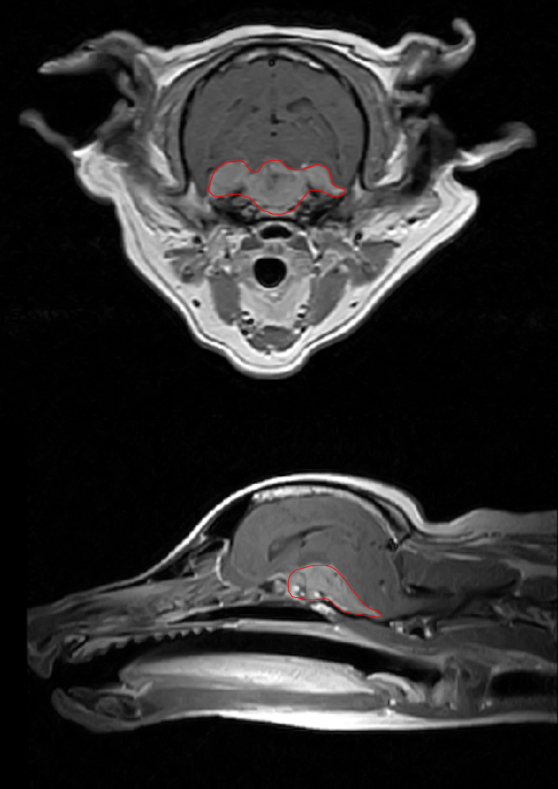

診断書とMRIに写る腫瘍

病理組織を取れない以上は断定できないものの、疑われたのは髄膜種でした

獣医師によるとどれ程の余命かは予見し辛く、腫瘍の成長速度も個体差が大きいとのこと

腫瘍の位置的に手術は難しく治療を行うなら放射線治療が第一選択になるとの話もあり、

腫瘍の大きさは非常に大きく、予断を許さない状態にあります

放置した場合は脳ヘルニア等を併発し急速に死亡してしまうケースもあり基本的には予後不良とのこと